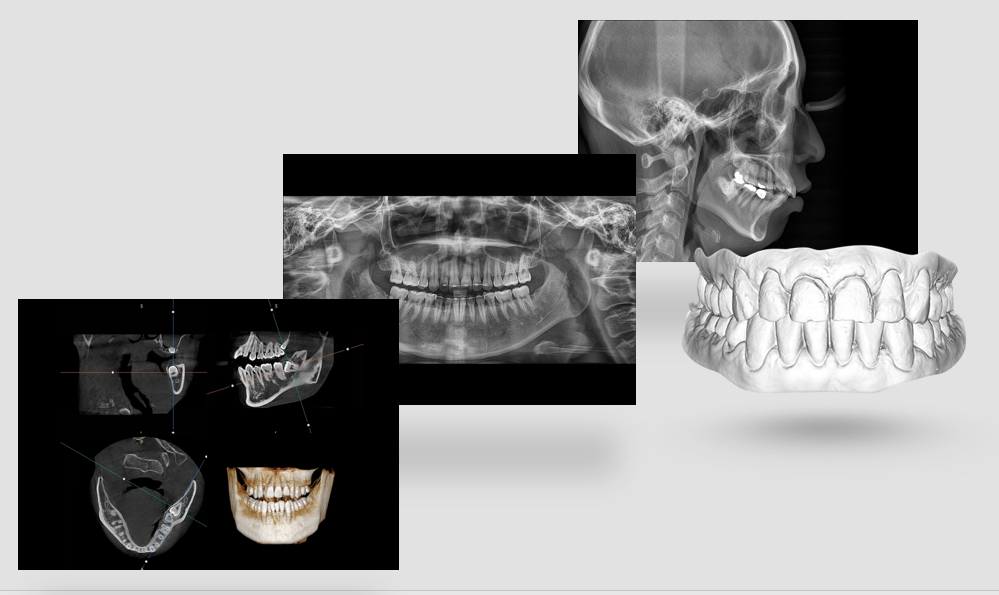

На выставке «Дентал Экспо Красноярск» успешно прошло заседание главных врачей во главе с Садовским Владимиром Викторовичем, Вице-президентом Общества Врачей России, Почетным Президентом СтАР, Директором Национального института исследований и адаптации маркетинговых стратегий (НИИАМС). Помимо насущных вопросов, руководители организаций региона обсудили преимущества и возможности использования стоматологического томографа Genoray Papaya 3D.

Несколько слов про преимущества:

- Уникальный моторизованный подбородочный упор с автоматическим позиционированием головы пациента в зависимости от типа и зоны исследования. Достаточно выбрать зону интереса. Все остальное делает сам аппарат!

- Плоскопанельный детектор имеет самую высокую в классе разрешающую способность